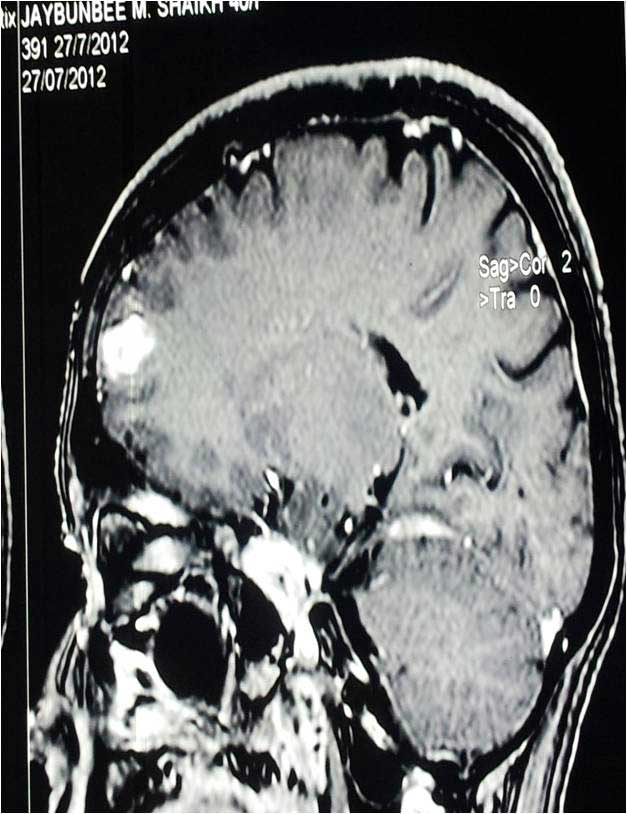

Cavernoma Pre Op Mri